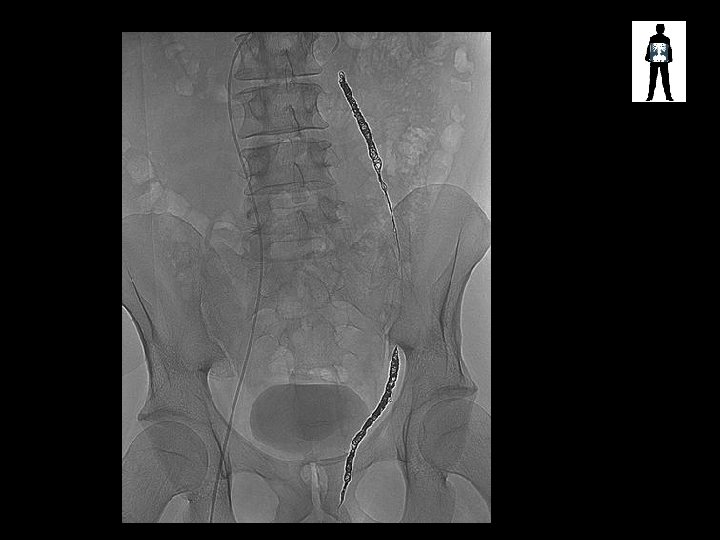

Small bowel pattern Surgical clips Artefacts? ? Embolisation coils SMALL BOWEL OBSTRUCTION

Varicocele Embolisation coils

Varicocele Embolisation Coils • Varicocele – enlarged scrotal vein – Causes pain, swelling, leads to infertility – Treated via embolization with coils or embolic fluid